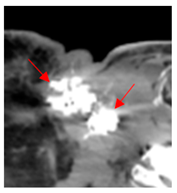

| 1 | 75–100 | 860 | ![]() Axial post-contrast fat-suppressed T1-weighted MRI shows a solidly enhancing left retroarticular tumor. | ![]() Axial CT image obtained 1 day after injection shows the NBTXR3 nanoparticles (arrows) in the tumor with leakage into the surrounding soft tissues. |